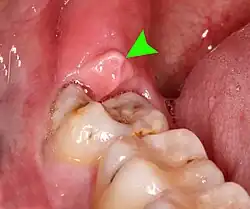

Impacted wisdom teeth without communication to the mouth, that have no pathology associated with the tooth, and have not caused tooth resorption on the blocking tooth, rarely have symptoms.[11] The chances of developing pathology on an impacted wisdom tooth that is not communicating with the mouth is approximately 12%.[11] However, when impacted wisdom teeth communicate with the mouth, food and bacteria penetrate to the space around the tooth and cause symptoms such as localized pain, swelling and bleeding of the tissue overlying the tooth. The tissue overlying the tooth is called the operculum, and the disorder is called pericoronitis which means inflammation around the crown of the tooth.[5]: 141 Low grade chronic periodontitis commonly occurs on either the wisdom tooth or the second molar, causing less obvious symptoms such as bad breath and bleeding from the gums. The teeth can also remain asymptomatic (pain free), even with disease.[7]

Pericoronitis is an infection of the operculum of a partially impacted wisdom tooth. It can be treated with local cleaning, an antiseptic rinse of the area and antibiotics if severe. Definitive treatment can be excision of the operculum, however, recurrence of these infections is high. Pericoronitis, while a small area of tissue, should be viewed with caution, because it lies near the anatomic planes of the neck and can progress to life-threatening neck infections.[14]: 440–441